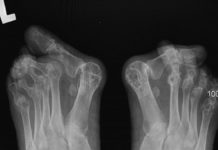

Reumatoidalne zapalenie stawów w obrębie kończyny dolnej – opis przypadku

Reumatoidalne zapalenie stawów jest chorobą autoimmunologiczną o nieznanej etiologii. Dotyka głównie stawów dłoni oraz stóp. Jest to choroba nawracająca, która nie jest wyleczalna.Celem pracy...